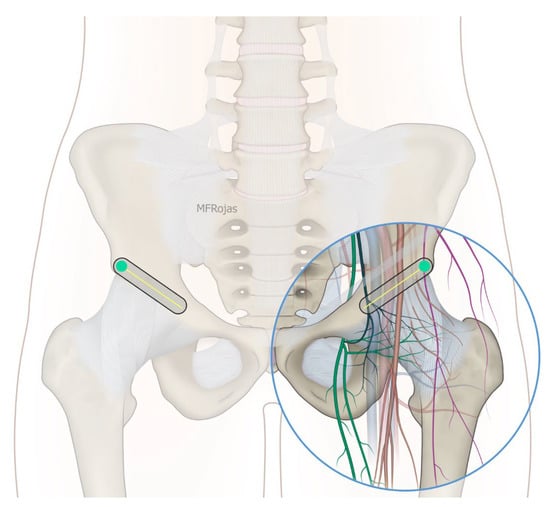

In addition to the classical PENG injection, our modified approach highlighted the addition of pericapsular infiltration in the iliopsoas plane to cover the low articular branch of the femoral nerve and a sagittal approach to target the ONAB. The algorithm was still used to perform diagnostic blocks, followed by alcohol neurolysis 10 min later for those with a positive diagnostic block in the same setting under real-time ultrasound guidance (Philips Affiniti 70, 5–12 MHz linear probe or 1–5 Hz curved probe depending on the depth of the target). In the modified approach, the procedure consisted of 3 needle insertions with the use of 22-gauge 10 cm Quincke needles. The first needle for the high femoral nerve articular branches (high FNAB branches) and AON was inserted in the same way as the PENG approach between the anterior inferior iliac spine (AIIS) and the iliopubic eminence (IPE) deep to the psoas tendon (Figure 2 and Figure 3). A second needle for the low branches of FNAB was inserted in-plane from lateral to medial and advanced through the sartorius, rectus femoris and iliopsoas muscles. The final needle position was in the plane superficial to the iliofemoral ligament medial to the rectus femoris tendon over the femoral head (Figure 4 and Figure 5). The third injection for the obturator nerve articular branches was used to target the caudal aspect of the inferomedial acetabulum (IMA) by scanning in a sagittal plane with a caudal-to-cephalad needle trajectory. The precise localization of the caudal aspect of the IMA could be first approached via the ordinary way (an oblique scan) as described in our first case series [5]. The probe was slowly rotated obliquely until the acetabulum, femoral head, and neck were aligned in the same plane, with the superomedial acetabulum coming into view. The probe was then slid caudally with the end point being the presence of the acetabulum without the femoral head. This referred to the location of the inferomedial acetabulum. The probe was then adjusted until the IMA was in the middle of the image, followed by rotating the probe by approximately 60 degrees (Figure 6). In this scan, the pectineus, the caudal aspect of the IMA and, occasionally, the obturator externus were seen. The ONAB could be visualized in the wedge of the subpectineal space directly adjacent to the IMA. Before any needle insertion, the probe was tilted slightly medially towards the obturator foramen to look for the acetabular/posterior branch of the obturator vessels which are usually deeper than the ONAB. The needle was then inserted from caudal to cephalad in-plane until the needle tip reached the wedge space consisting of the ONAB (Figure 7). In case the wedge space could not be clearly visualized, the needle tip would then be advanced until touching the caudal bony surface of the IMA directly underneath the pectineus. Then, 0.5–1% ropivacaine (4, 3 and 2 mL, respectively) was injected into the above three landmarks. The needles were left in situ during the diagnostic test while their positions were reconfirmed by ultrasound before 100% alcohol was injected into the above targets with volumes in a 1:1 ratio between alcohol and local anaesthetics. A decrease of ≥50% in composite pain score on hip flexion at 45 degrees 10 min after the blocks signified a positive diagnostic block. As a post-neurolysis routine manner, stylets were reinserted before needle withdrawal.

Our modified approach to the ONAB would have the following advantages over the ordinary oblique approach published in our first case series [5]. First, in patients with hip fracture, their fractured limb is commonly externally rotated. This would deviate the femoral vessels to overlay the needle trajectory to the ONAB at the inferomedial acetabulum (Figure 8). This sagittal approach can reliably avoid the femoral vessels in the trajectory. Second, the sagittal scan allows us to visualize the acetabular/posterior branch of the obturator vessels underneath the ONAB, and this can minimize the chance of inadvertent puncture of these small vessels. Third, the ONAB anatomically courses along the caudal aspect of IMA instead of the lateral aspect of IMA [24]. The modified approach can potentially target the ONAB more precisely. Lastly, the modified approach allows the ONAB to be visualized clearly in non-obese patients, whereas the ordinary approach only relies on a rough bony landmark of IMA. Although a large volume of subpectineal injection may lead to a spread to the motor branch of obturator nerve [27], we did not identify any case with neurological deficit along the obturator nerve distribution in our study.

Figure 6. Schematic diagram showing the sagittal plane at the IMA with femoral vessels avoided. Reproduced with permission from Dr Maria Fernanda Rojas Gomez (Bucaramanga, CO). Green dot: transducer mark.